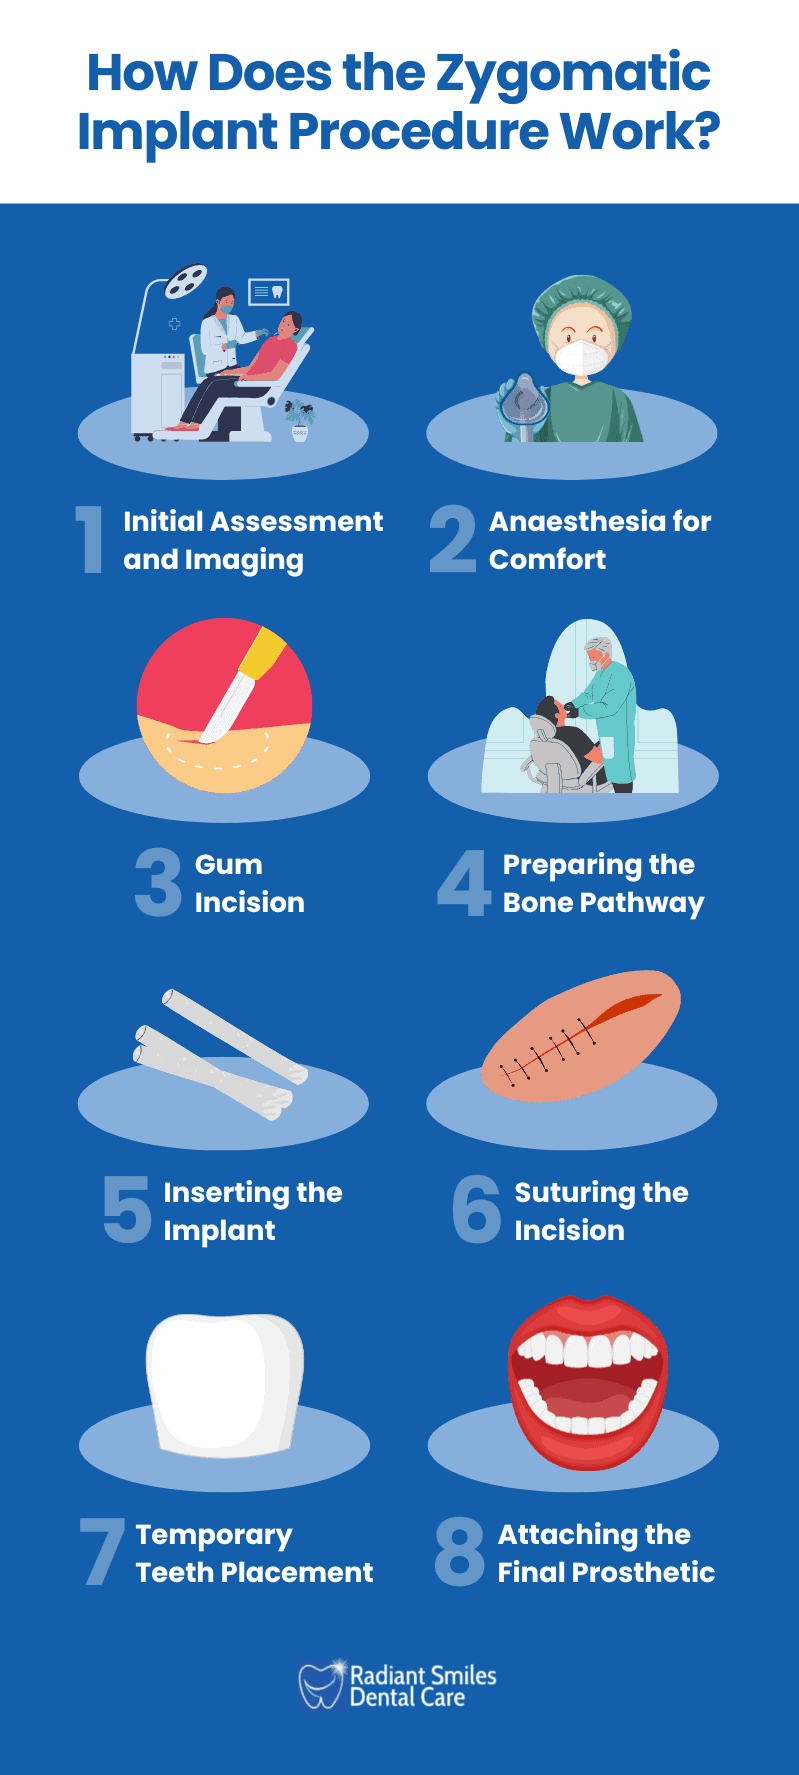

How does the Zygomatic Implant Procedure Work?

The zygomatic implant procedures involve careful planning, precise placement of implants into the cheekbone, securing temporary teeth soon after surgery, and fitting permanent restorations once healing is complete.

The zygomatic implant procedures involve careful planning, precise placement of implants into the cheekbone, securing temporary teeth soon after surgery, and fitting permanent restorations once healing is complete.

1. Initial Assessment and Imaging

The process starts with a thorough evaluation, including 3D imaging, to assess the bone structure and determine the best positions for implant placement. This planning avoids important oral and maxillofacial structures like nerves and sinus cavities.

2. Anaesthesia for Comfort

Local anaesthesia, often combined with sedation, is used to keep the patient relaxed and free from pain throughout the procedure.

3. Gum Incision

A small incision is made in the gum to expose the bone. This step provides access for preparing the implant site.

4. Preparing the Bone Pathway

The surgeon carefully drills an angled pathway from the upper jawbone to the zygomatic bone using specialised tools. This makes sure the implant has a secure and stable fit.

5. Inserting the Implant

The long zygomatic implant is placed into the prepared pathway and anchored in the cheekbone, providing stability in cases of significant bone loss.

6. Suturing the Incision

The incision is closed with sutures, protecting the site and initiating the healing process.

7. Temporary Teeth Placement

In many cases, a temporary prosthetic is attached to the implants shortly after surgery. This provides functional and aesthetic benefits while the implants heal.

8. Attaching the Final Prosthetic

After the healing period, during which the implants integrate fully with the bone (osseointegration), a customised, permanent prosthetic is fitted. This final restoration is designed for durability and a natural appearance